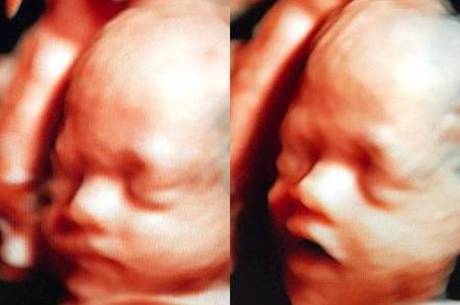

A nutricionista e digital influencer, com mais de 3,3 milhões de seguidores no Instagram, Bella Falconi fez a alegria de seus fãs na manhã desta quarta-feira (30) ao compartilhar um exame de ultrassom, em que aparece o rostinho de sua segunda filha, Stella.

Na legenda, Bella disse, toda emocionada: "Minha benção! Stella. Adorei te ver hoje filha! 1.250kg e 35 cm, já é uma bebezona".